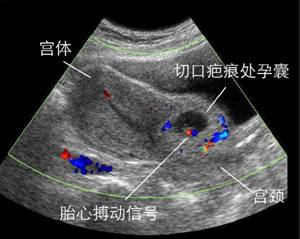

(图:疤痕妊娠)

千万小心疤痕妊娠

孕囊着床在子宫原疤痕处,常导致阴道大量流血以及晚期的子宫破裂,是较难处理的异常妊娠。这是剖宫产手术后再次妊娠一个严重的并发症,属于宫外孕的一种,非常凶险。如果孕早期出现先兆流产类似的腹痛出血症状,也有可能是疤痕妊娠的早期症状。一般子宫疤痕妊娠通过B超是能发现的,所以对于有过剖宫产史的女性,再次妊娠早孕时必须进行B超检查,早期发现有助于避免子宫破裂和出血,从而便于及时处理。